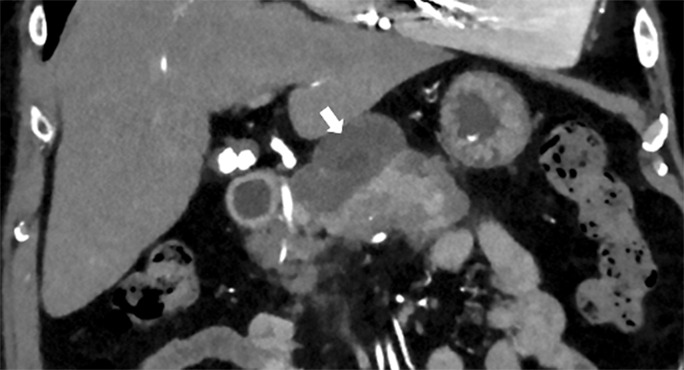

Case presentation: A 74-year-old PD patient presented with cloudy dialysate and subtle symptoms of malaise and abdominal pain. WBC was 26,000/µL, CRP was 250 mg/L, and dialysis effluent contained 1,047 leucocytes/μL (90% polymorphs). Infectious peritonitis was presumed, and antibiotic treatment started. However, dialysate cultures remained negative, effluent leucocyte count remained high, and clinical condition deteriorated. Abdominal ultrasound was unremarkable (pancreas not visible). Acute pancreatitis was diagnosed by elevated lipase level (serum: 628 U/L, dialysis fluid: 15 U/L) and CT scan. Disentangling etiological factors was challenging. The patient had gallstones, consumed alcoholic beverages, was recently on doxycycline and dialyzed with icodextrin. In addition, PD treatment itself may have been a contributory factor. Antibiotic therapy was stopped, and PD was temporarily suspended. Systemic and effluent markers of inflammation took 4 weeks to normalize. The patient did not regain his usual state of health until several weeks after discharge. Follow-up CT scan showed considerable pancreatic sequelae.